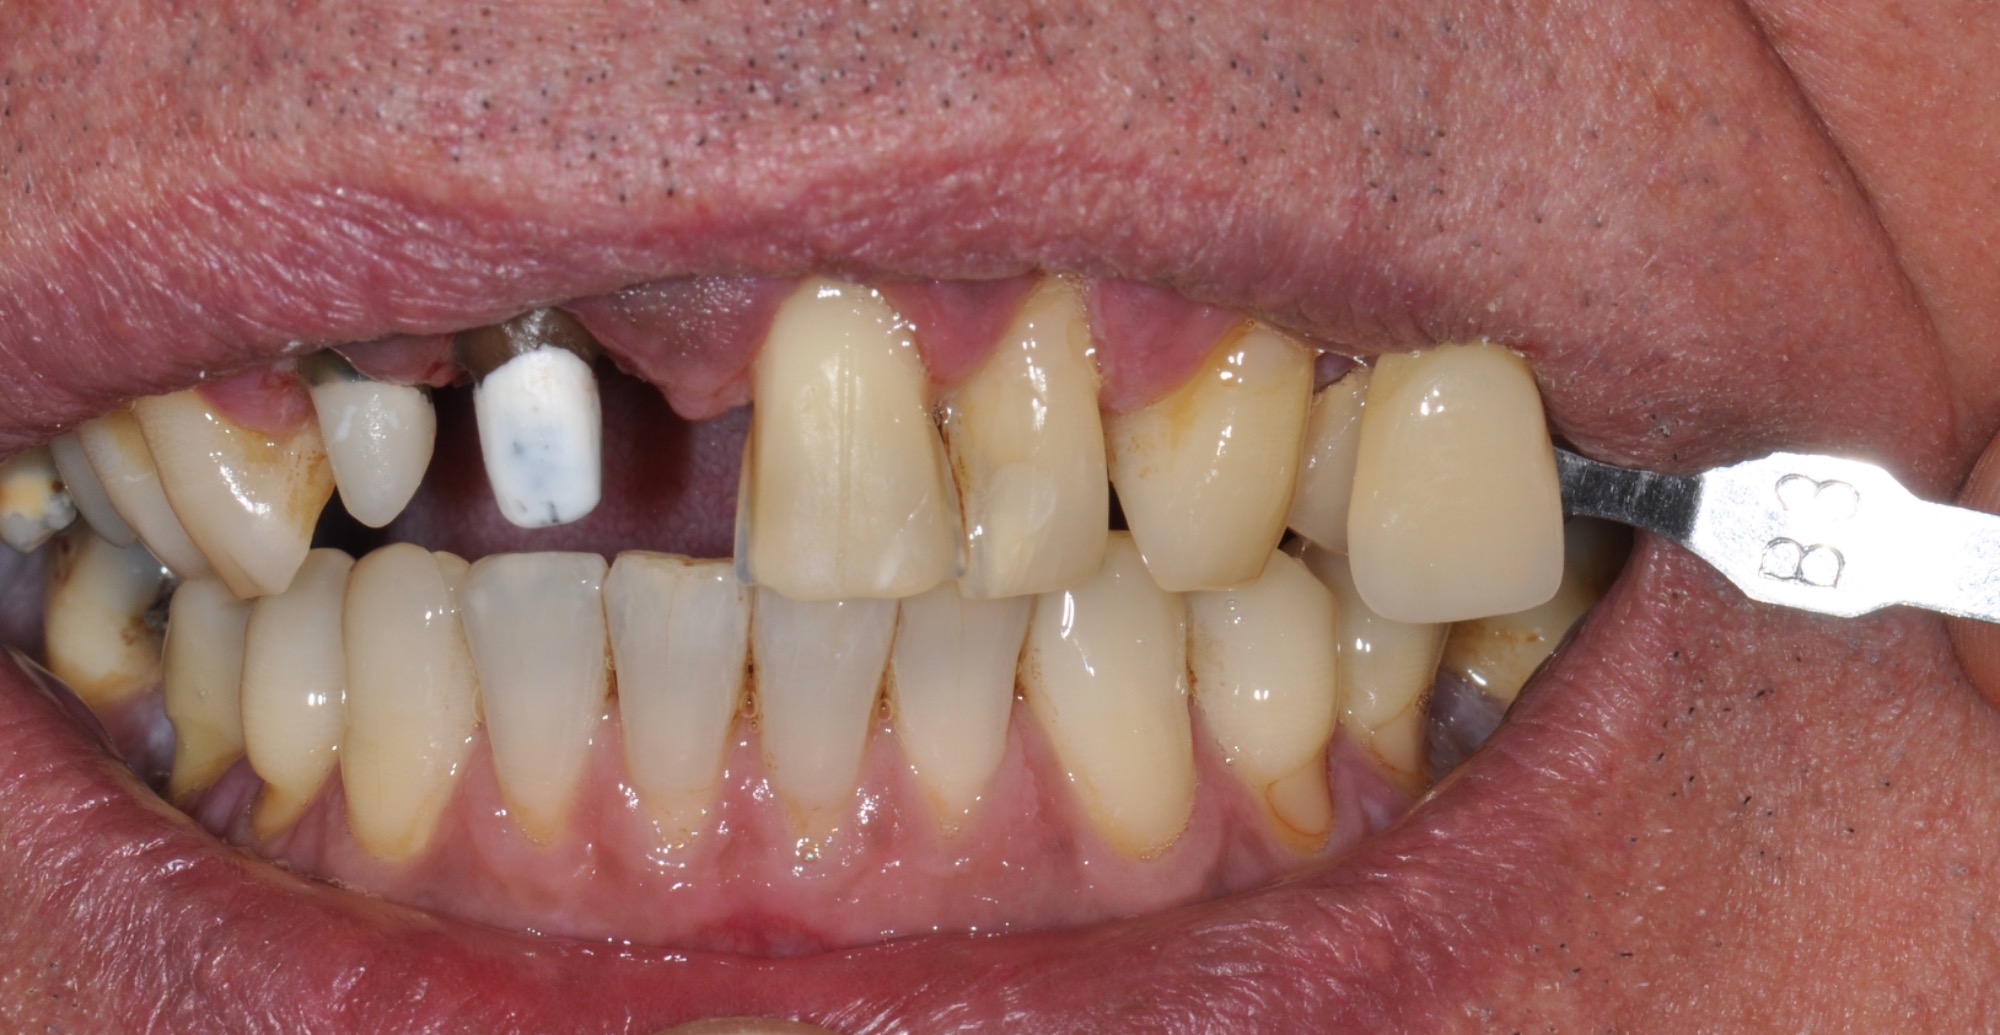

Teleskopierende Oberkieferbrücke mit Vorher- und Nachher-Situation des Patienten.

Teleskopierende Oberkieferbrücke. Wie die eigenen Zähne, aber einfach zu reinigen.